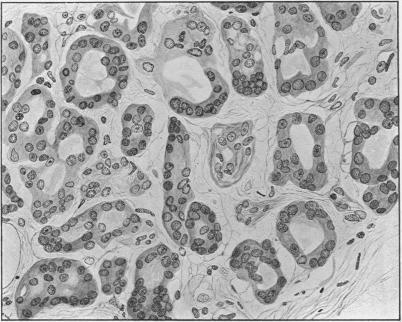

VII. Carcinoma of the Papilla of Vater.

Ann Surg. 1913 Mar;57(3):402-26. doi: 10.1097/00000658-191303000-00007.